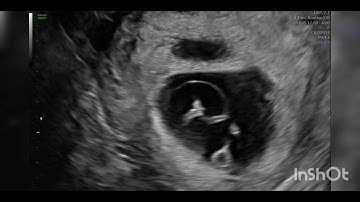

Twin reversed arterial perfusion (TRAP) sequence